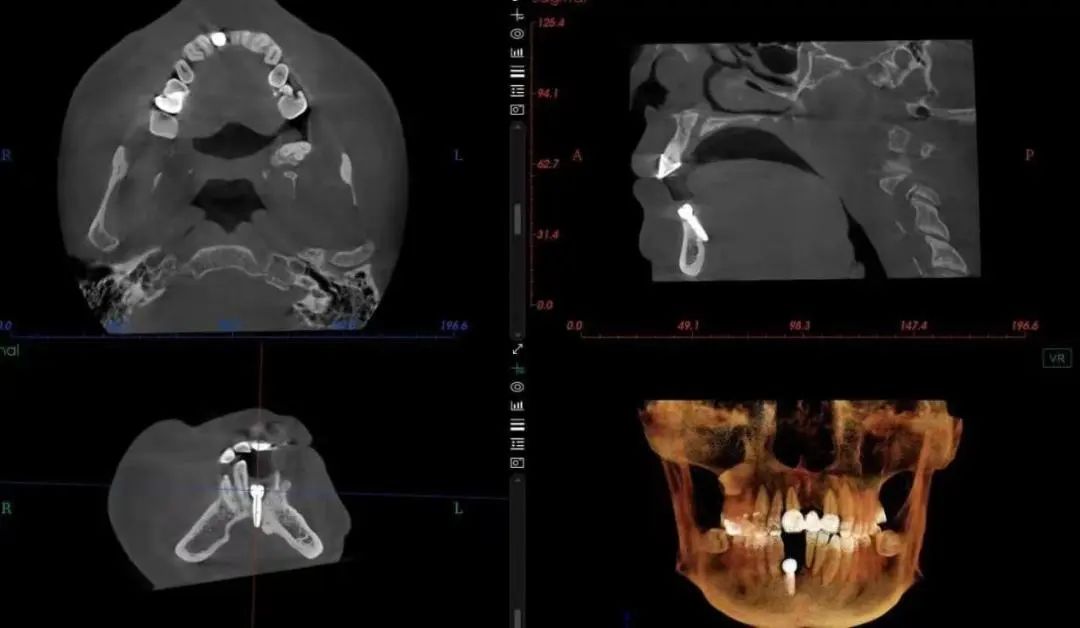

经排查,口底出血主要是由于在外院种植手术过程中损伤口底血管导致。